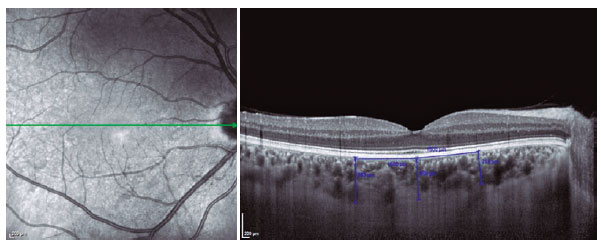

Binarization of the choroidal area was performed with the Image-J Version 1.50a software (National Institutes of Health, Bethesda, MD, USA; Figures 2 and 3). The EDI-OCT image was opened with Image-J, and 3000-µm wide areas with margins of 1500 µm temporal to the fovea was chosen. The choroidal area was defined as the region from the retinal pigment epithelium to the chorioscleral border, and the borders were set manually with the Image-J ROI Manager. Three choroidal vessels with lumens >100 µm were selected using the oval selection tool and the mean reflectivity of the luminal areas were determined. The Niblack method was used for the binarization of the choroidal image. Then, the image was converted to 8 bits and adjusted using the Niblack auto local threshold. The luminal area was determined with the threshold tool. After adding the distance between the pixels, the choroidal, luminal, and stromal areas were automatically calculated for the 2 groups. The light pixels were accepted as the stromal area; and the dark pixels, as the luminal area (12). The choroidal vascularity index (CVI) was calculated as the ratio between the luminal and total choroidal areas.

12-fig02tb.jpg)